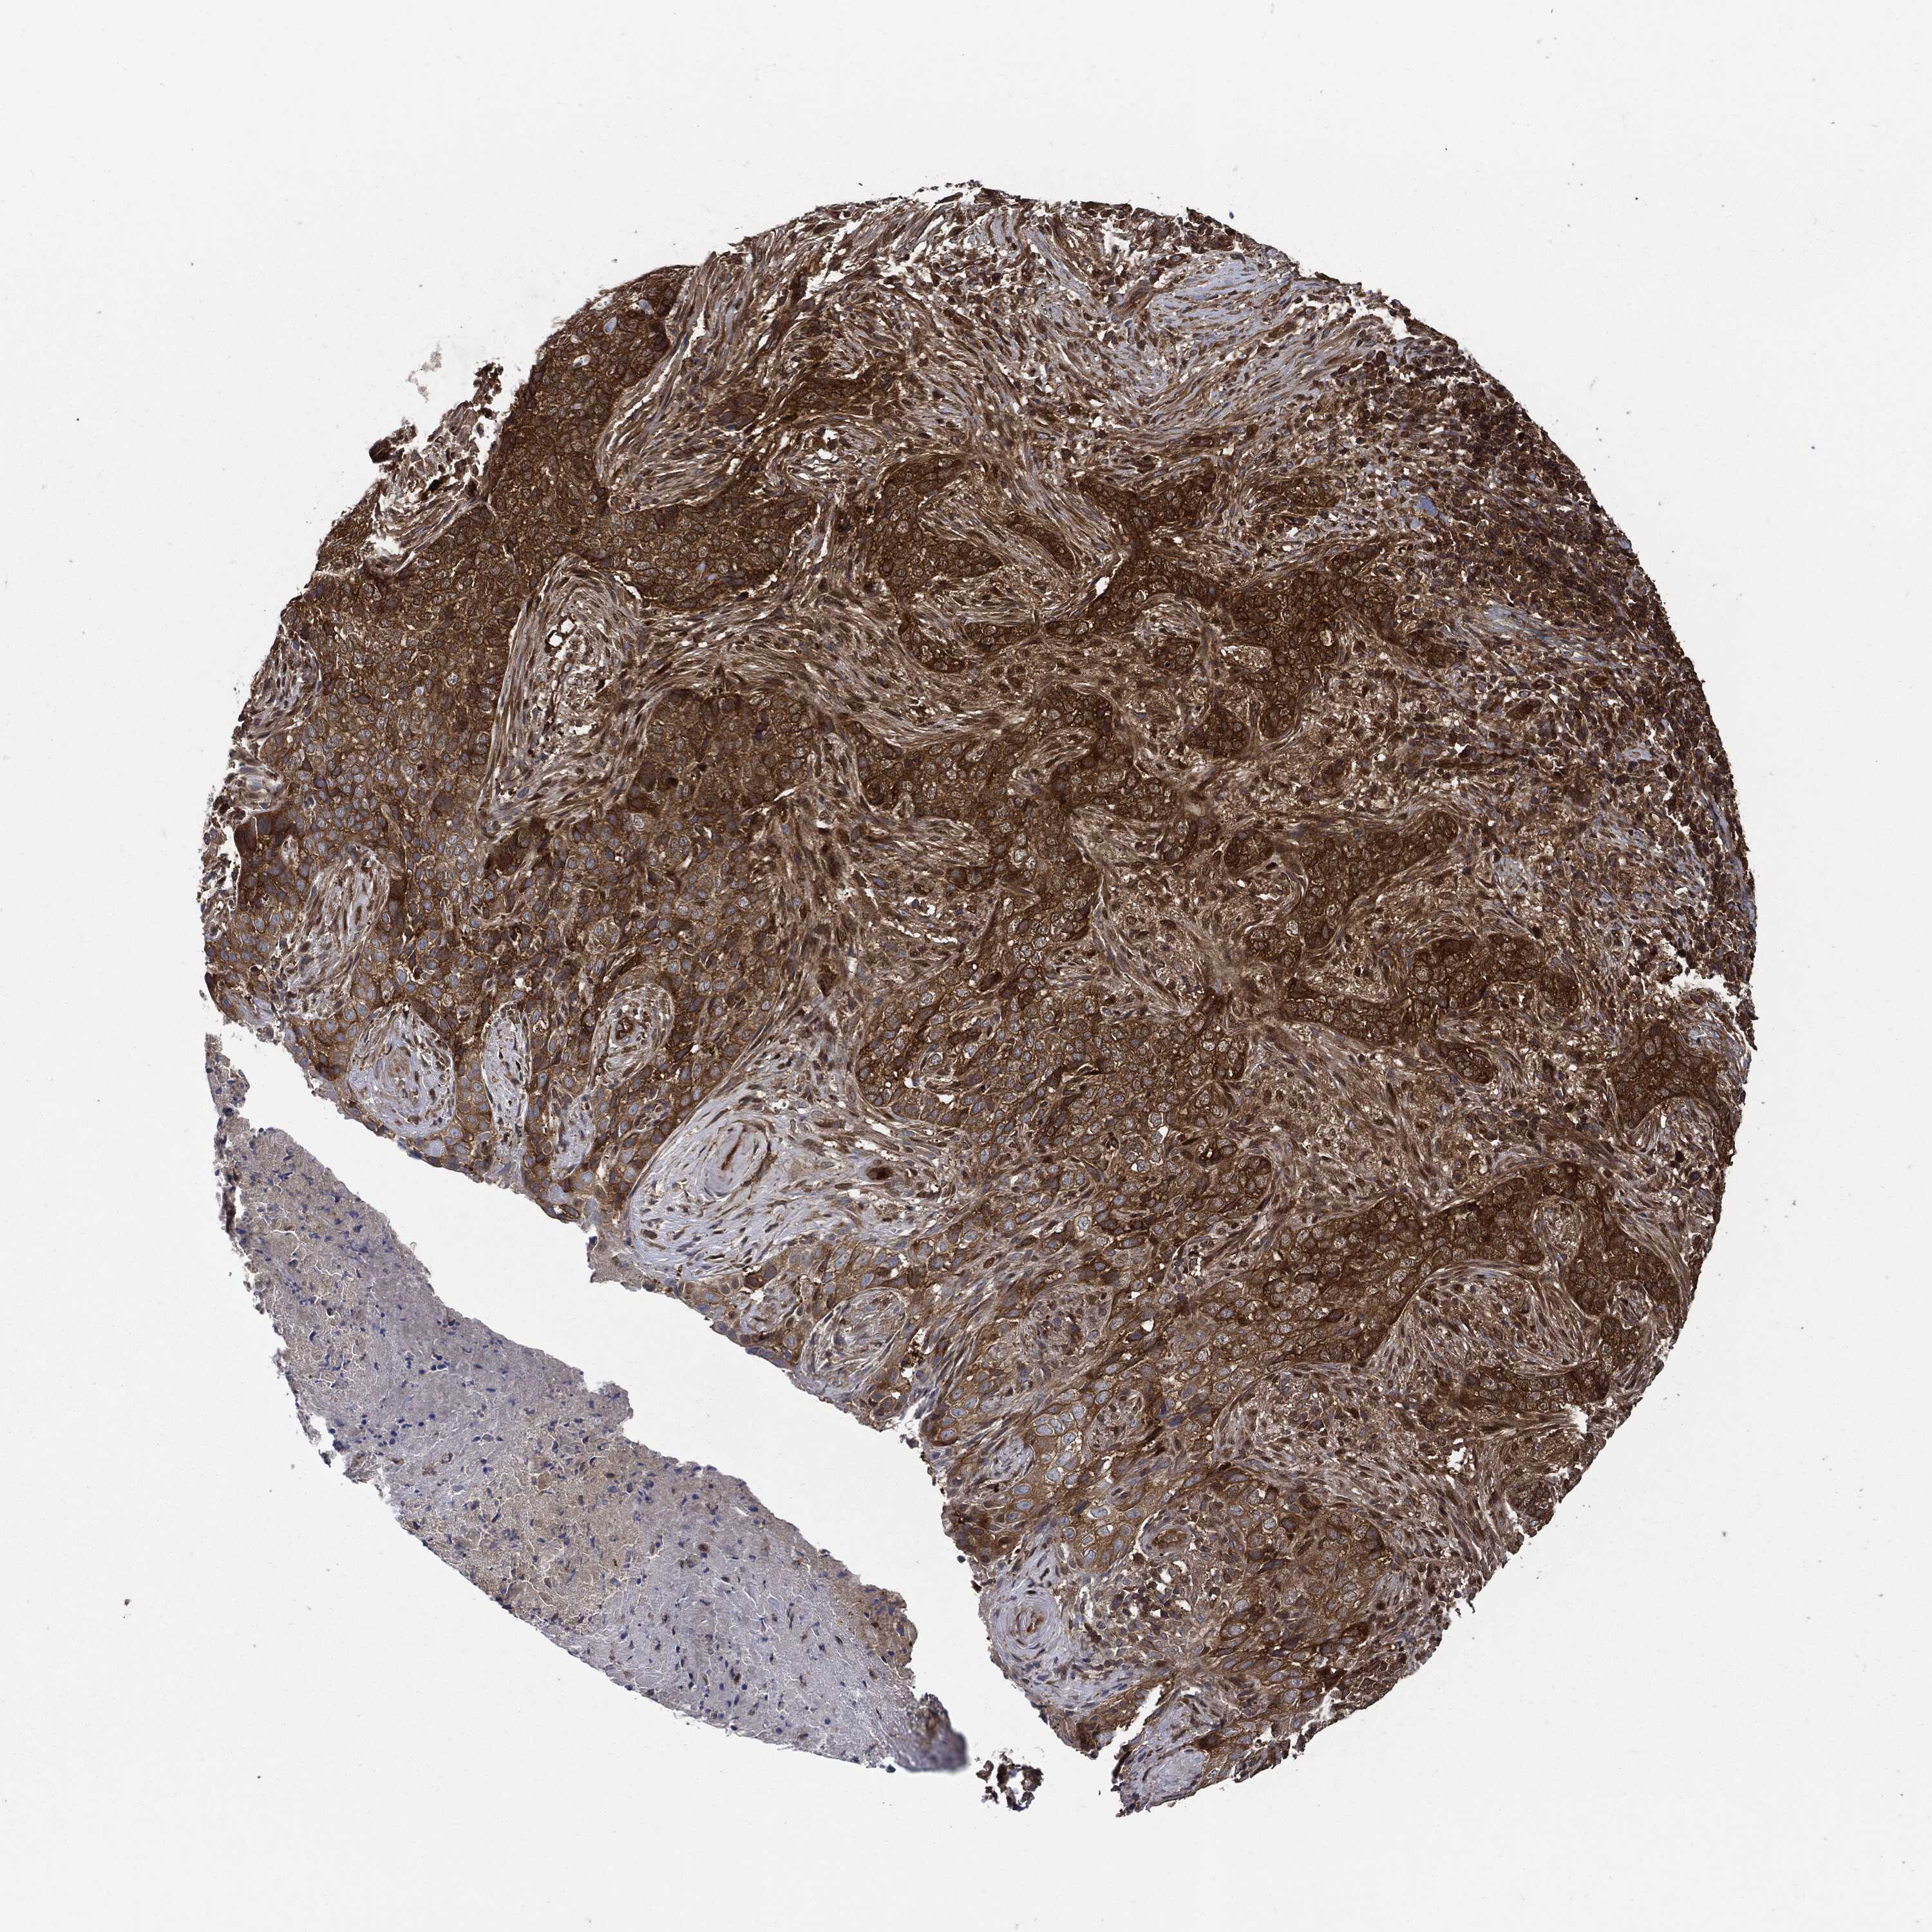

SKIN CANCER - Protein expressioni

A mouse-over function shows sample information and annotation data. Click on an image to view it in a full screen mode. Samples can be filtered based on level of antibody staining by selecting one or several of the following categories: high, medium, low and not detected. The assay and annotation is described here.

Antibody stainingi

Antibody staining in the annotated cell types in the current human tissue is reported as not detected, low, medium, or high, based on conventional immunohistochemistry profiling in selected tissues. This score is based on the combination of the staining intensity and fraction of stained cells.

Each image is clickable and will lead to virtual microscopy that enables deeper exploration of all samples and also displays staining intensity scores, fraction scores and subcellular localization as well as patient and tissue information for each sample.

HPA030419

HPA030420

HPA030422

CAB025196

CAB080286

CAB080287

Staining

High

Medium

Low

Not detected

Intensity

Strong

Moderate

Weak

Negative

Quantity

>75%

75%-25%

<25%

None

Location

Nuclear

Cytoplasmic/membranous

Cytoplasmic/membranous,nuclear

Basal cell carcinoma

Squamous cell carcinoma, NOS

Squamous cell carcinoma, metastatic, NOS